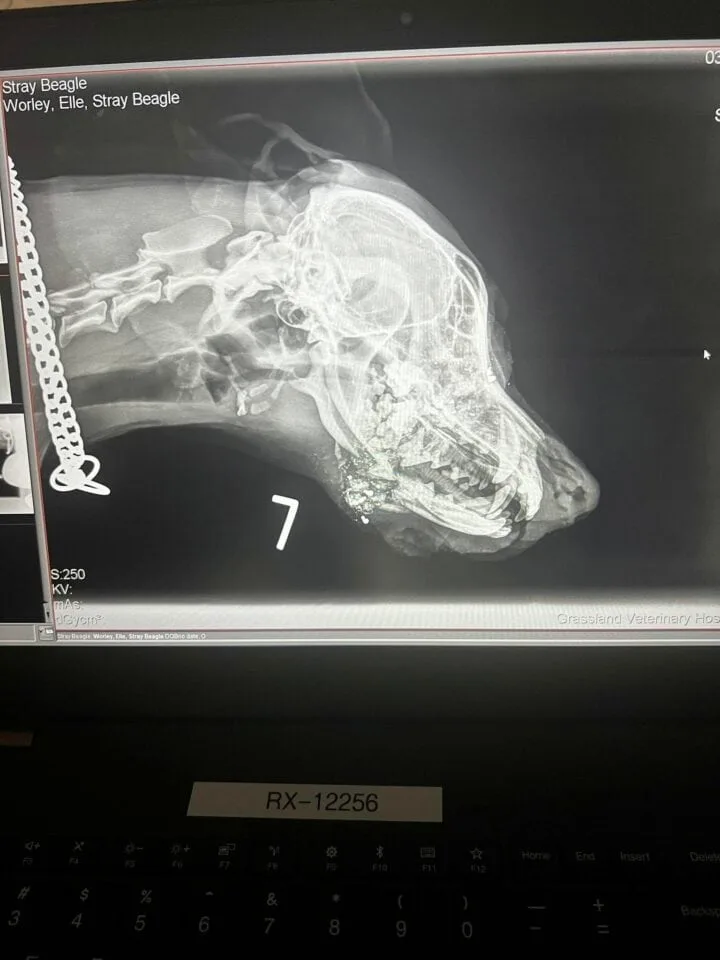

The X-rays brought heartbreaking news. Juni had been shot twice in the jaw, and the bullets had narrowly missed hitting her brain.

The cruelty of what had been done to her was overwhelming. Elle was devastated. How could someone do something so horrible to such a gentle soul?

The veterinarians explained that Juni would need immediate surgery to repair the damage. Without it, she would suffer unbearable pain and possibly not survive.